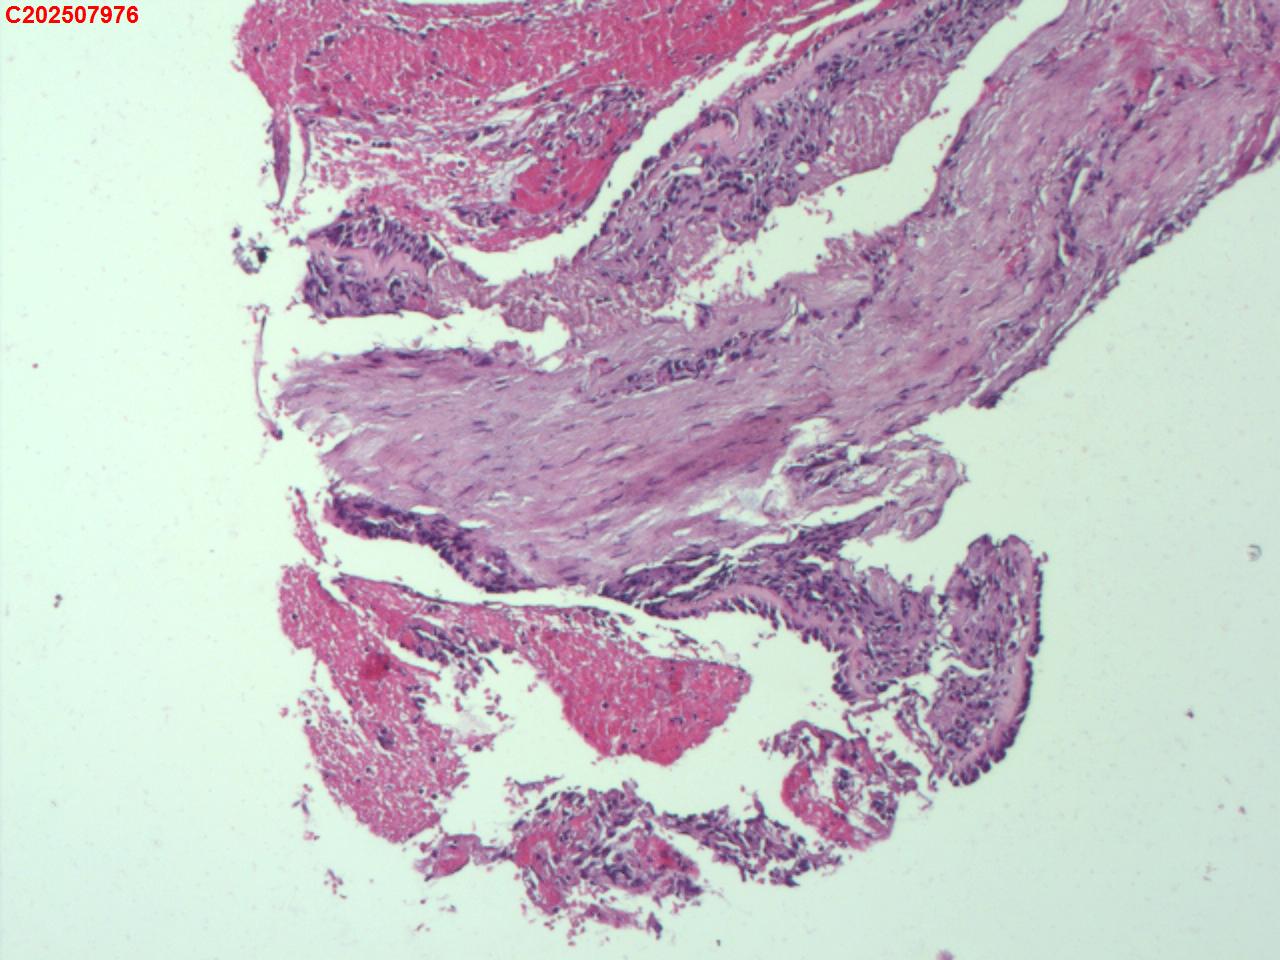

右肺上叶开口处 气管镜咬检

大体所见

右肺上叶开口上缘处可见肉芽增生,予咬检。

感觉:炎性纤维组织增生